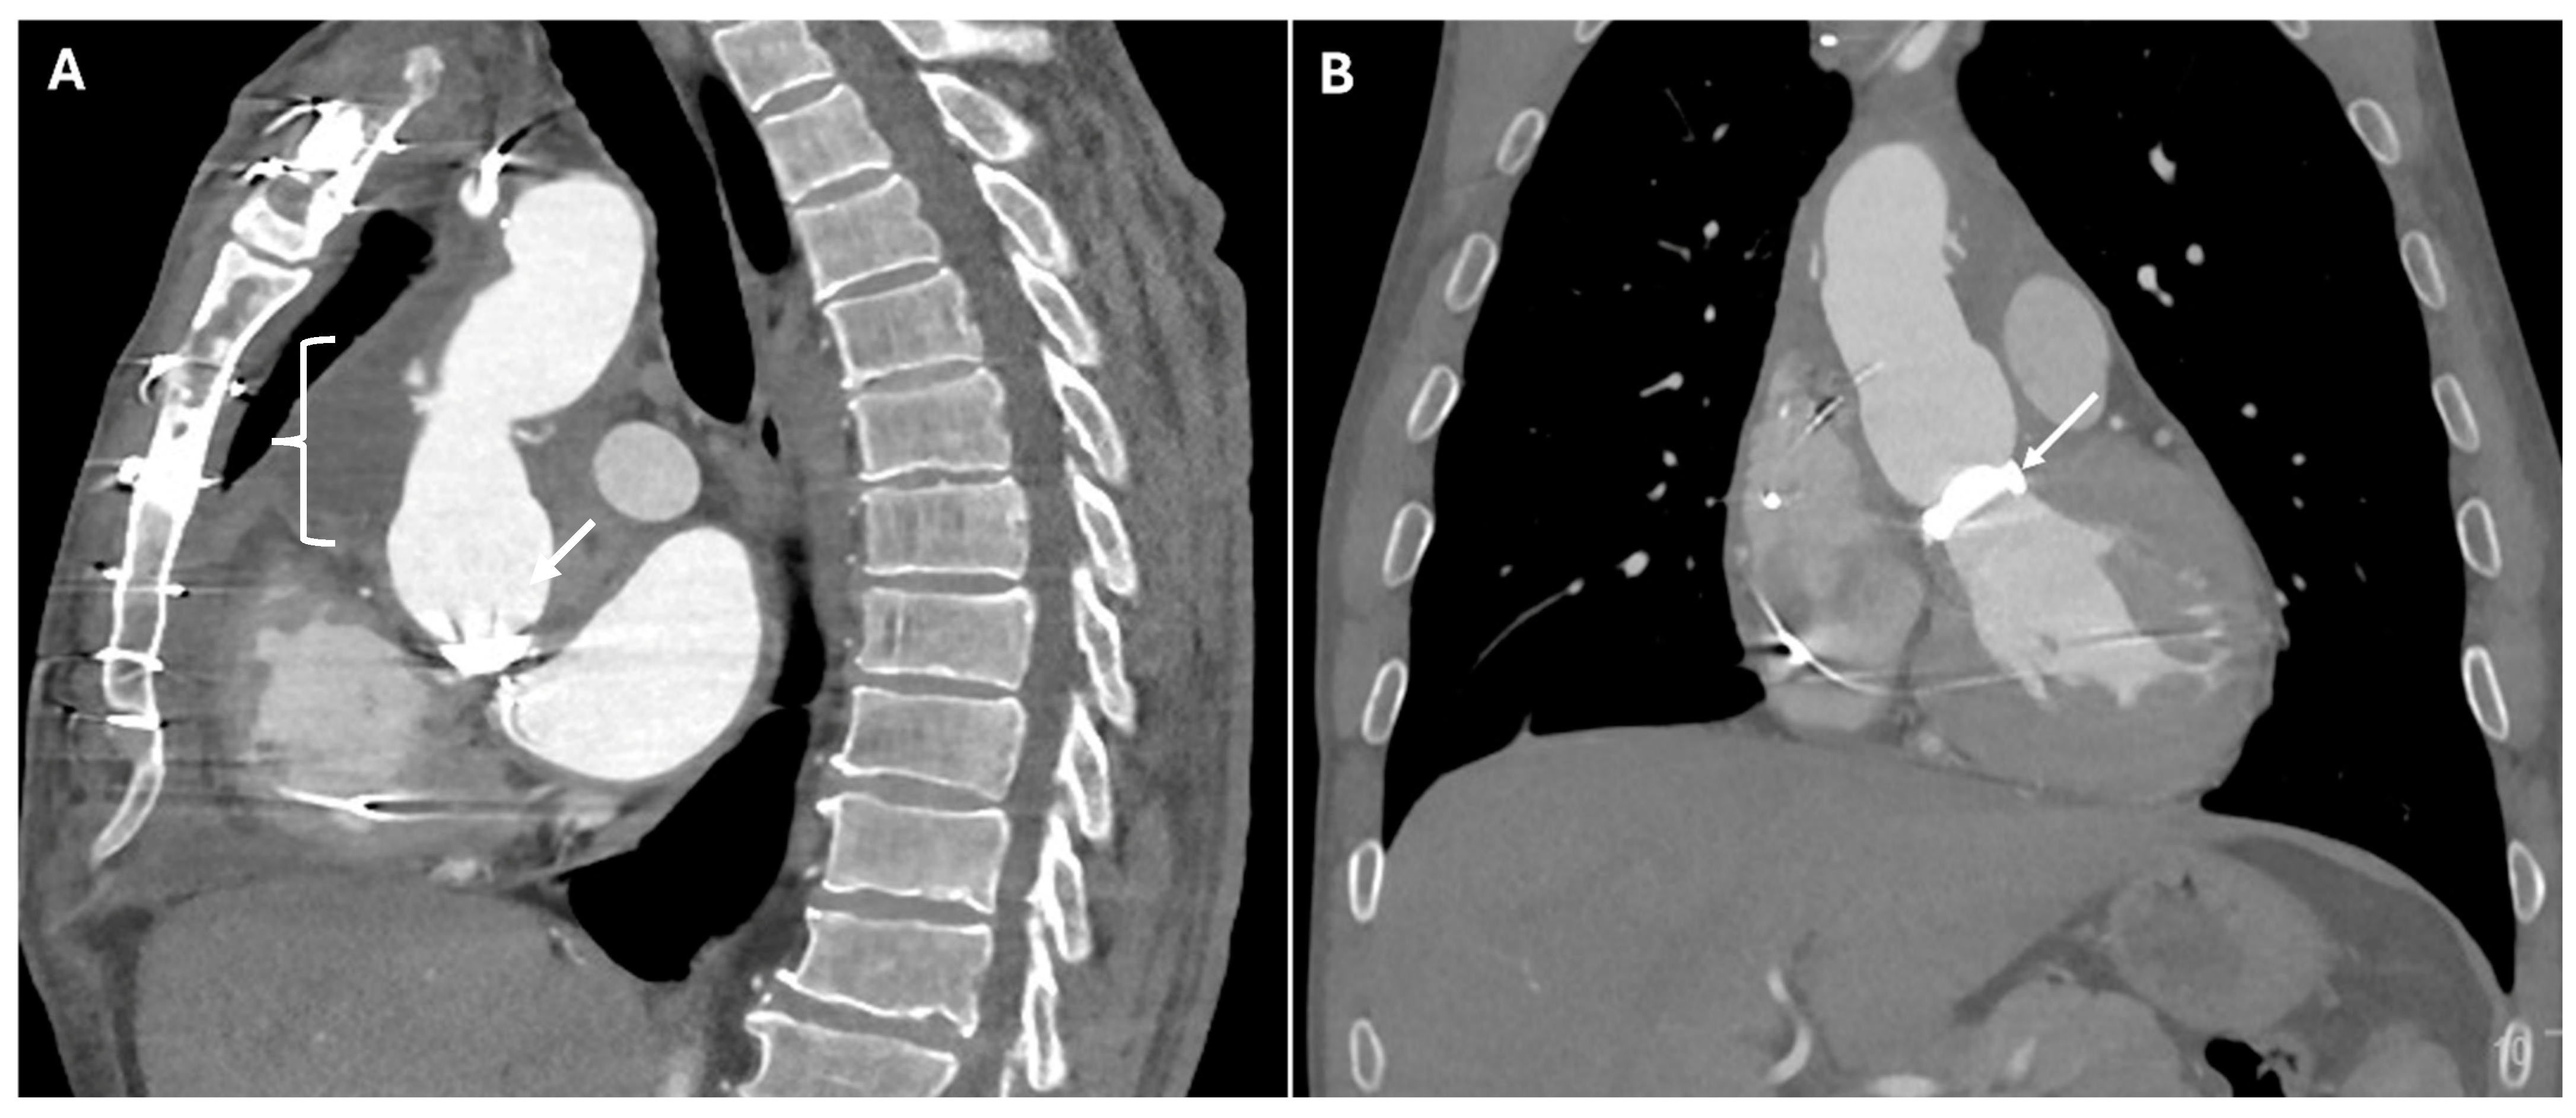

| Pseudoaneurysm | Suture failure, infection, chronic mechanical stress | Contrast-filled sac adjacent to graft, narrow neck | High rupture risk |

| Endoleaks (TEVAR) | Incomplete sealing, graft migration | Persistent contrast enhancement outside stent graft lumen | Can lead to aneurysm expansion and rupture |

| Aorto-Esophageal or Aorto-Bronchial Fistulas | Erosion of graft into adjacent structures | Contrast extravasation into esophagus or bronchial tree, adjacent air | Massive hemorrhage |